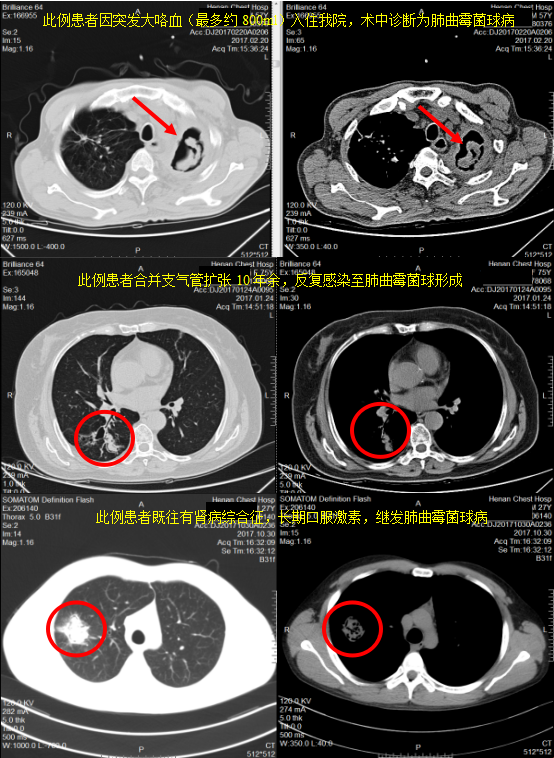

肺曲霉菌球病怎么诊断呢?胸部CT是其主要诊断方法,具有慧眼识珠的医生一看就明白了(肺曲菌球的CT多表现为空洞内有团块影,可随体位改变而变动,周围呈半月形或新月形透光区,常为单个,上叶多见,亦可以呈多发件分布于多个肺叶),再结合既往病史(如服用激素史、结核病史、糖尿病史等),基本能明确大多数(但确切诊断需要病理明确,如可以经CT下肺穿刺活检,支气管镜活检等)。如下图几例曲菌球病变: